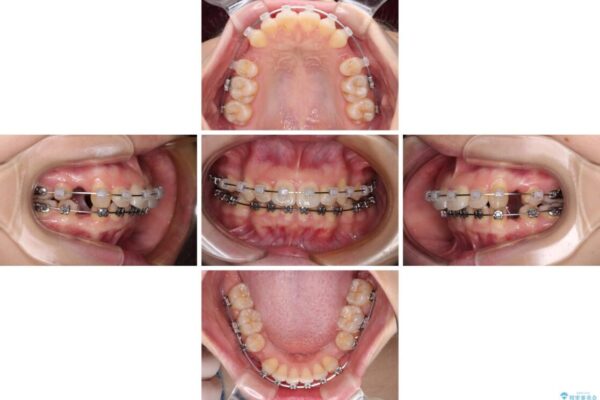

治療途中

• 【モニター】口が閉じられない ワイヤー装置での抜歯矯正 治療途中画像

※写真にある上顎装置はメタルブラケットではありません。メーカー在庫都合などにより別の装置を使用しております。